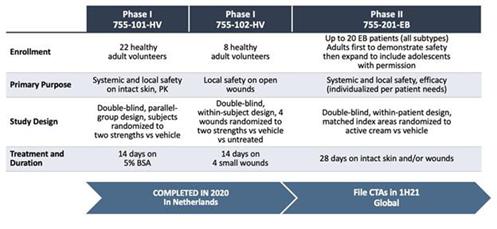

In addition to relief of symptoms, inflammation, pain, and others, we believe INM-755 may impact the underlying disease by enhancing skin integrity in a subset of EB patients. We have completed more than 30 preclinical pharmacology and toxicology studies to investigate the effects of CBN. Several of these nonclinical studies explored the effect on important symptoms such as pain and inflammation. In in vitro pharmacology studies, CBN demonstrated activity in reducing markers of inflammation. CBN upregulated expression of a type of keratin called keratin 15, or “K15”, which might lead to skin strengthening and reduced blister formation in EB simplex, or “EBS”, patients with mutations in another keratin called keratin 14, or “K14”. The anti-inflammatory activity of CBN may be beneficial in healing chronic wounds caused by prolonged inflammation. Following a review of our toxicology studies, the Netherlands National Competent Authority and Ethics Committee approved the initiation of a Phase I clinical study in healthy volunteers. We have safety data with INM-755 cream in 22 healthy adult volunteers from our first Phase I study (755-101-HV) in which subjects had the INM-755 cream applied to their upper backs daily for 14 days. An interim safety analysis of the first 16 subjects was reviewed by the Netherlands National Competent Authority and Ethics Committee and determined to be adequate to allow initiation of the second Phase I study testing INM-755 cream on small wounds. That second study has completed and we now have safety data for INM-755 cream applied to small open wounds daily for 14 days in 8 healthy adult volunteers.

A regulatory application to support our first Phase I clinical study in healthy volunteers with INM-755 (755-101-HV) was submitted November 4, 2019 and approved December 6, 2019. The initial Phase I clinical study evaluated the safety, tolerability, and pharmacokinetics of INM-755 cream in healthy volunteers with normal, intact skin; the volunteers had cream applied once daily for a period of 14 days. All subjects in this first clinical trial completed treatment and evaluations by March 27, 2020. A regulatory application was approved April 17, 2020, for a second Phase I clinical study of healthy volunteers to test the local safety and tolerability of applying sterile INM-755 cream to small wounds once daily for 14 days. As with the initial Phase I trial, the second trial (755-102-HV) was conducted with two different drug concentrations and a vehicle control. Enrollment began in early July 2020 and the clinical trial completed treatment and evaluations at the end of September 2020. The safety of INM-755 will continue to be assessed throughout its clinical development.

INM-755 cream was well tolerated in the two Phase I clinical studies in healthy volunteers and the next step will be to study INM-755 cream in patients with EB (Study 755-201-EB). Regulatory applications to support this global trial have been filed and are under review by the National Competent Authorities and Ethics Committees in Germany, France, Italy, Austria, Israel, Greece and Serbia, with patient enrollment expected to begin in 2H21.